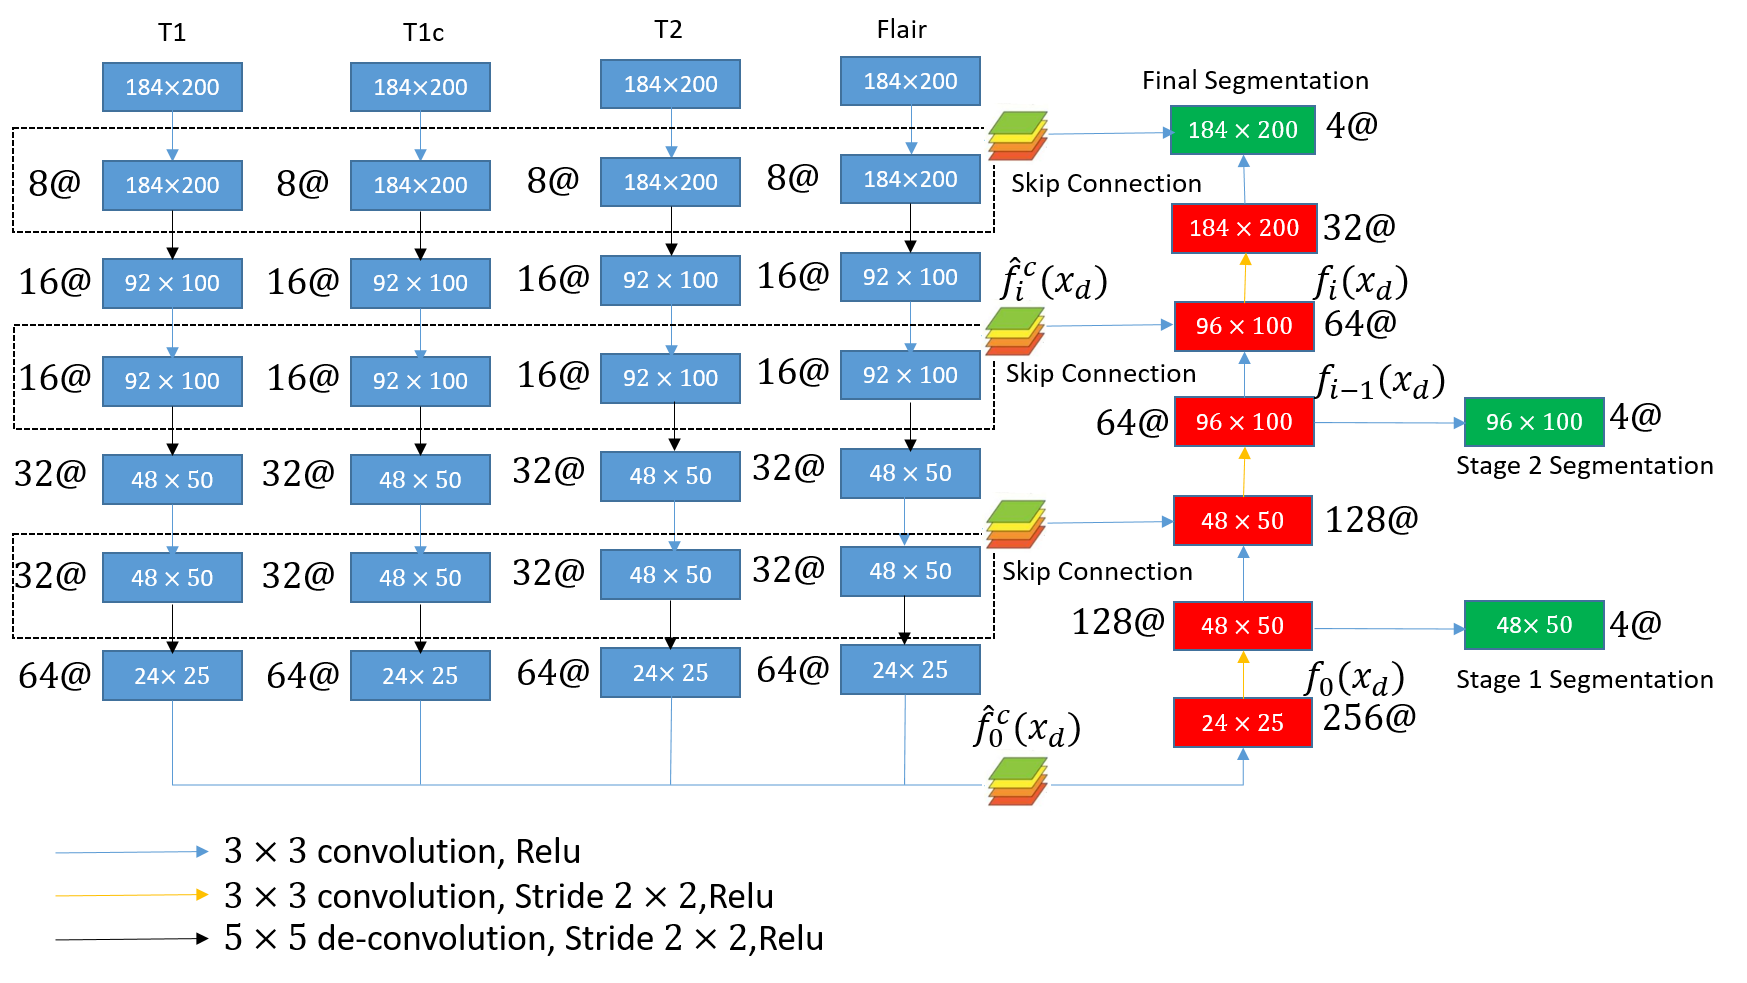

Our basic model architecture follows U-net, as shown in Fig. 1. Each modality is fed into the model as one channel. Blue box indicates separated encoding path of the multi-channel MR image input. Red box indicates decoding path following the encoding of multi-channel input on various levels of feature maps. Green box indicates multi-stage segmentation outputs. Encoding path includes multiple feed-forward down-sampling convolutional layers after each channel input. And it ends up with 64 features map of resolution from each input channel. Individual encoding path of each channel have independent sets of parameters and have no connection with each other before decoding. Though cross-channel filter banks could be used to extract features by contrasting different input channels at early stage in a more straight-forward way, our separated feature maps on four different channels can be used to encode abstractions of segmentation information that is tolerant on channel loss. Our separately encoded feature maps are fused and decoded in our following decoding path.

In our network’s decoding path, higher resolutions of segmentation outputs are created by successively up-sampling in a bottom-up approach and mixing channel-separate feature maps at various levels. Up-sampling operations use de-convolution operators. Channel-separate feature maps created at encoding path are fused by convolution operators. The features maps at the end of encoding path from each input channel are fused to create bottle-neck feature maps at the same resolution. Two levels of inter-mediate feature maps from each input channel are fused with the feature maps created along the decoding path. We fuse intermediate feature maps from encoding path with the ones from decoding to create skip connections. Our decoding path includes a total of three stages of successive mixing and up-sampling. After each stage, we also generate a segmentation at the same level of the same resolution by convolutions. The final segmentation outputs with the same resolutions as input MR images are generated after the final stage.

We train on the lower resolution segmentation outputs at the intermediate feature maps to force our network learn a hierarchical representation of segmentation related information from coarse to fine, where the structural information is encoded at the lower resolution feature maps and the boundary level information is encoded at the higher resolution feature maps. In this way, we generate our segmentation outputs by sequentially inferring area of pathology structures and exact boundaries.